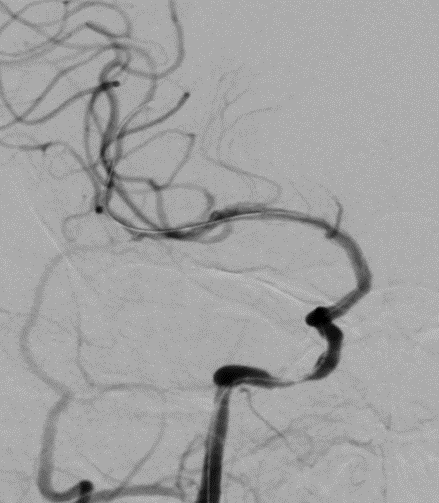

术后造影。

导丝怎么扩【载药时代 球扩天下】NOVA DES®颅内药物洗脱支架在颈内动脉颅内段重度狭窄的应用二例!_https://www.jmylbn.com_新闻资讯_第33张